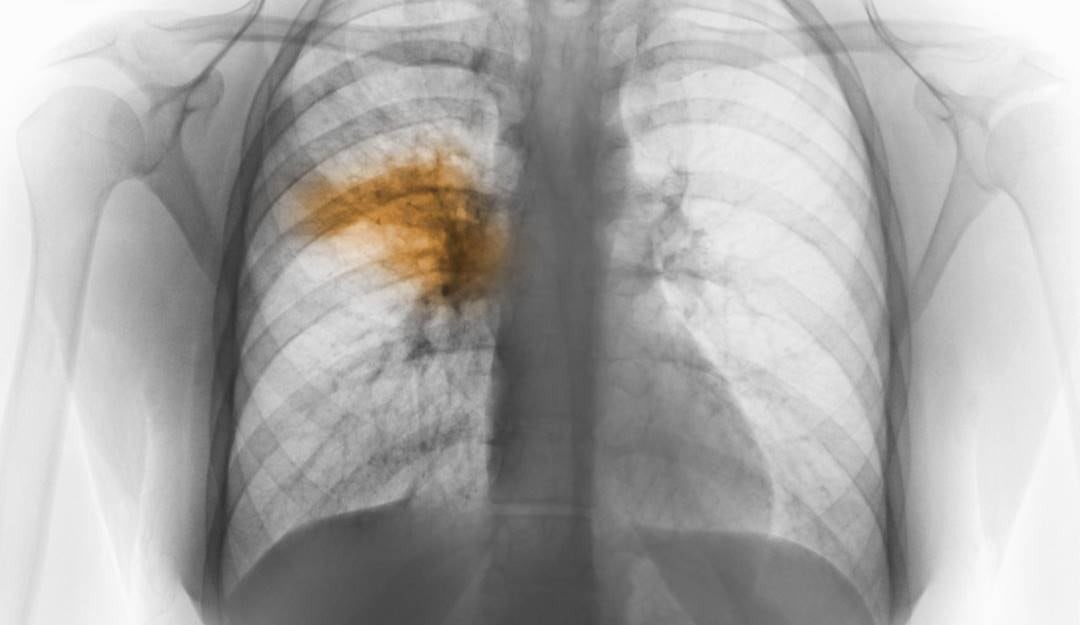

Sanatorio en Argentina fue aislado por casos de neumonía de origen desconocido

Dos personas fallecieron por la neumonía bilateral

Las autoridades sanitarias de Tucumán, en el norte de Argentina, ordenaron el aislamiento preventivo por siete días del Sanatorio Luz Médica, ubicado en donde se detectaron seis casos de neumonía bilateral cuyo origen es desconocido.

Según informó el Ministerio de Salud de Argentina, los seis casos registrados corresponden a cinco trabajadores de la salud y a una paciente que iniciaron síntomas entre el 18 y el 22 de agosto.

Hasta el momento, los casos mortales son dos, sin embargo el ministro de salud pública, Luis Medina Ruiz, aseguró que desde el 22 de agosto no se registran nuevos casos.